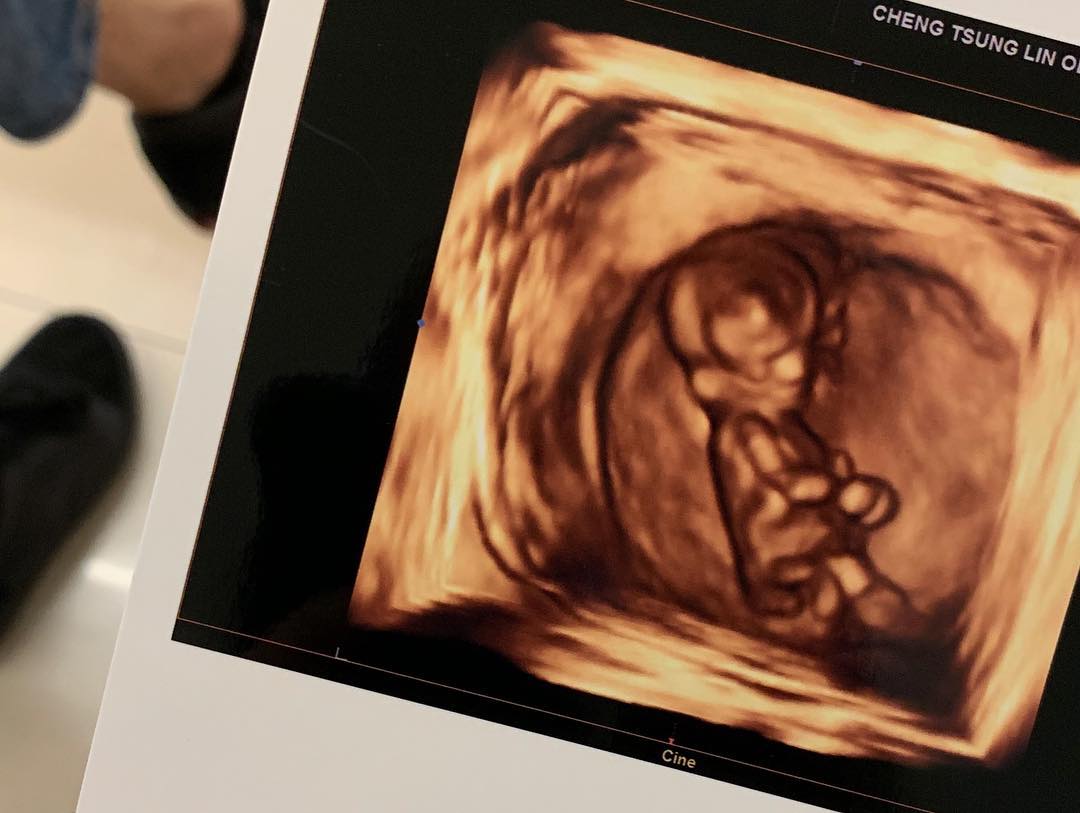

陳艾琳今天在社群網站宣布懷孕喜訊,微微隆起的小腹,正孕育著3個月的小生命,更PO出寶寶的超音波照,開心直說「怎麼會有這麼可愛的小生物!」看著寶寶在肚子裡手舞足蹈,讓身為準媽媽的她開心不已。聽著醫生講解孕婦該注意的事項,Alex也在一旁拿著筆記本一筆一筆的抄寫著,可見她對陳艾琳的細心呵護。最後,她在貼文中寫著「我知道我們一家四口(還有每天偷喝我滴雞精沒喝到就狂喵的多奇)會很幸福的,最後謝謝我們的爸媽,你們是最酷的家長。」